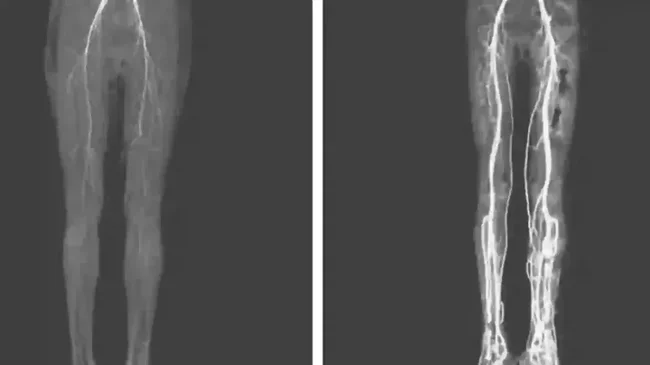

The legs of a girl infected with "St. Anthony's fire"

So, that's what I'm talking about, oh yeah, not long ago a young American woman came down with a hellish burning sensation in her legs. The examination showed damage to the limbs bordering on gangrenous.

The girl was saved, but the toe on one foot had to be cut off. The doctors thought for a long time about what had happened to her. They looked through the archives and only then realized that this young lady had caught a greeting from the Middle Ages.